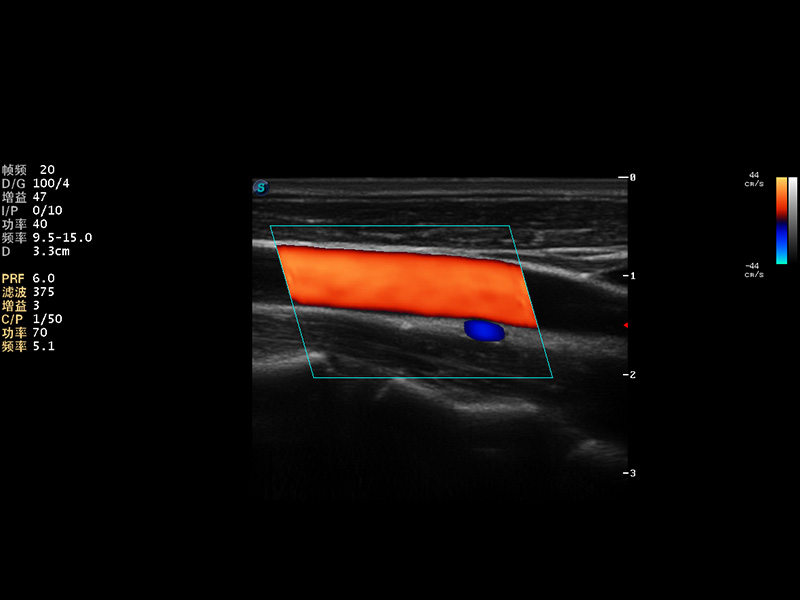

S9便携式彩色多普勒超声诊断仪是竞技宝(JJB)官方网站研发的高端便携彩超设备,外观设计新颖、产品性能卓越。S9在便携超声领域采用了突破传统的触摸屏交互设计,并以先进的软件硬件技术和设计理念,为您带来清晰的图像质量、稳定的工作性能和便捷的操作体验。

AutoC智能血流追踪